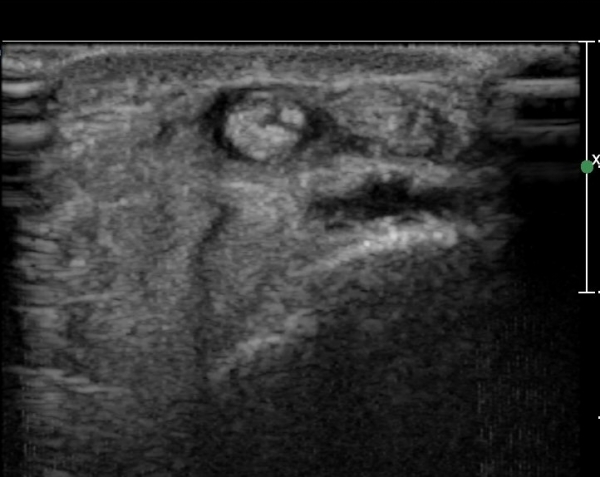

¿ä°ñ °æ»óµ¹±â ºÎÀ§¿¡¼­ tunnel I Ⱦ´Ü¸é°Ë»ç¿¡¼­ ´Ü¹«Áö½ÅÀü°Ç(EPB)ÀÇ ºÎÁ¾ ¹×

°ÇÁÖÀ§ ¼ö¾×Àú·ù°¡ °üÂûµÊ(»çÁø 1, 2)